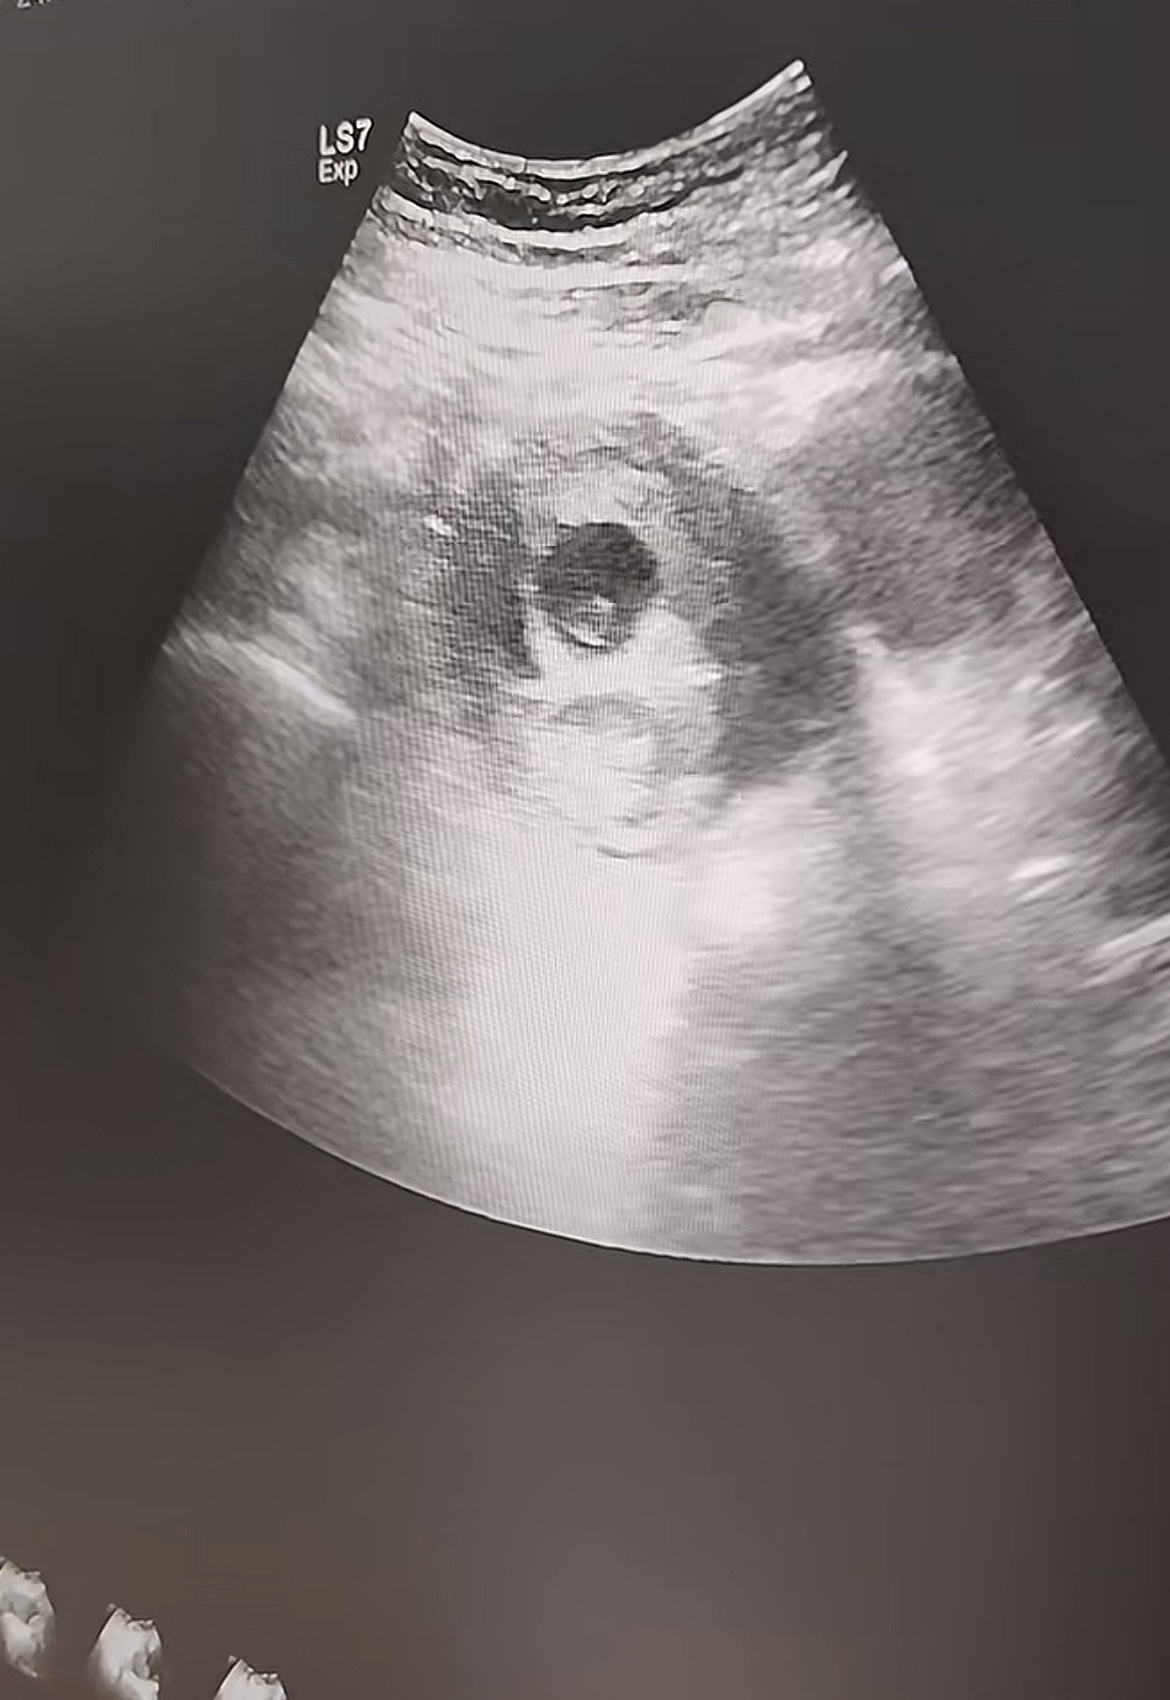

我们的核心优势在于 “可视” 。手术在高清超声影像引导下进行,医生可以清晰看到宫腔内孕囊的准确位置与大小。手术器械能精准定位、吸附,只对目标组织进行吸取,有效避免了对正常子宫内膜的过度刮拭,极大降低了子宫损伤和穿孔的风险。